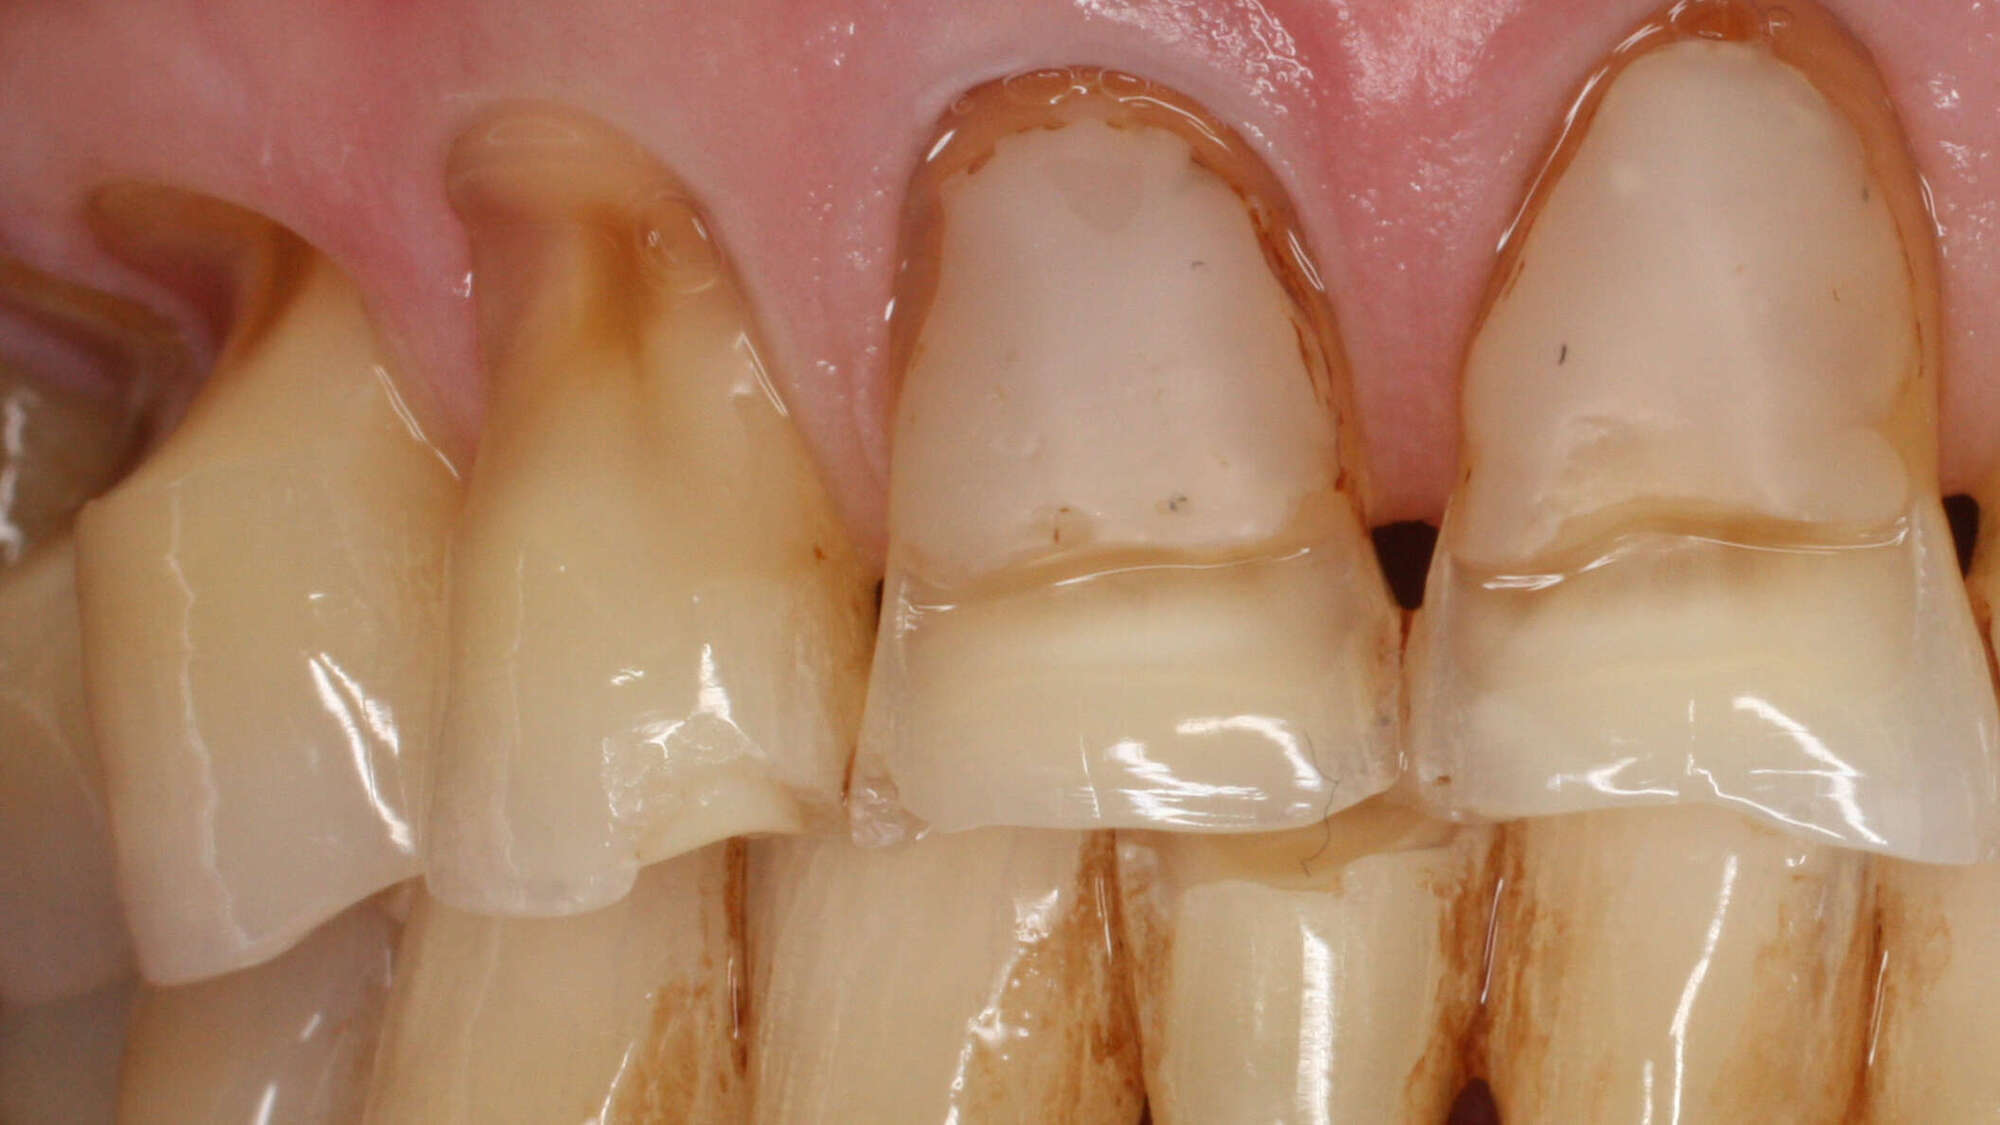

L’abrasion des dents : l’usure due aux gestes mécaniques extérieurs

L’abrasion se manifeste lorsque les dents sont soumises à des frottements extérieurs répétés, le plus souvent en lien avec des habitudes d’hygiène ou de comportement. Une brosse à dents trop dure, une technique de brossage trop vigoureuse ou l’usage fréquent de dentifrices abrasifs peuvent, au fil du temps, entraîner une rétraction des gencives et une usure de l’émail au niveau du collet.

On observe également cette forme d’usure chez les personnes qui utilisent leurs dents comme outil, par exemple pour ouvrir des emballages ou ronger des objets. L’abrasion est aujourd’hui assez fréquente, notamment chez les personnes qui recherchent un brossage « très efficace » sans réaliser que la pression excessive fragilise les dents.

dents usées par frottement d'une brosse à dents abîmée

Pour l’éviter, il est essentiel d’adopter une technique de brossage plus douce, d’utiliser une brosse à dents souple et un dentifrice non abrasif, tout en supprimant les habitudes délétères.

Si l’abrasion a provoqué une perte de substance ou une hypersensibilité, il est possible de restituer la forme d’origine des dents grâce à des composites esthétiques appliqués directement au fauteuil, ou, dans certains cas, grâce à des restaurations prothétiques plus élaborées.